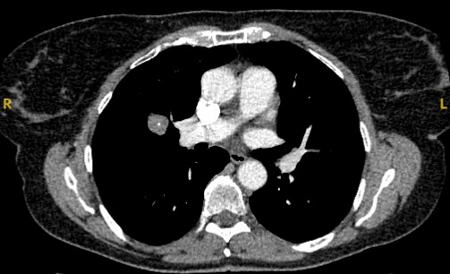

Computed tomography (CT) section with soft tissue configuration, showing a right lung hamartoma, as incidental finding in an asymptomatic patient. Note the central calcification and several small spots of fat within the nodule. This nodule was stable over a 12 year period and no intervention required

From the collection of Dr George Tsaknis, MD, PhD, FRCP(London), MRQA, MAcadMEd, PGCert; used with permission